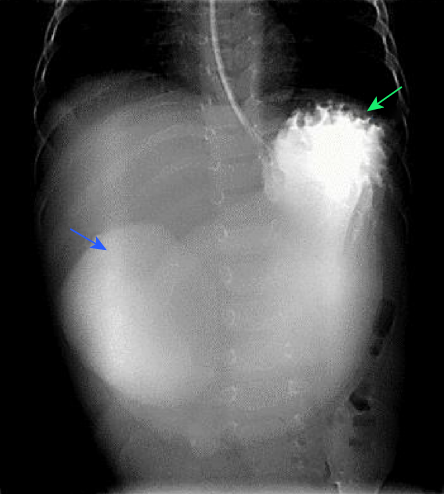

Laboratory investigations revealed hyponatremia (sodium: 118 mmol/L; (reference range: 135–145), hypokalemia (potassium: 2.6 mmol/L; reference range: 3.5–5.5 mmol/L), hypochloremia, (chloride: 77 mmol/L; reference range: 97–107 mmol/L), and metabolic alkalosis (bicarbonate: 42 mmol/L; reference range: 22–29 mmol/L). Ultrasound abdomen showed a partially distended stomach with normal pyloric width (5.5 mm) and length (12 mm). Sweat test and renin and aldosterone levels were normal. Urine sodium and urine/serum osmolality were also normal. A water-soluble upper gastrointestinal meal and follow-through demonstrated a markedly distended stomach and duodenal bulb [Figure 1]. Informed consent was obtained from the patient’s mother.

Figure 1: Anterior-posterior image of the upper gastrointestinal study shows a markedly distended stomach filled with water-soluble contrast (blue arrow). Oral contrast is seen in the first part of the duodenum (green arrow), with no contrast seen beyond this point.